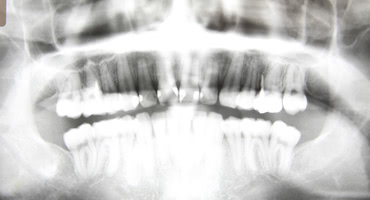

インプラント治療をする際に大きな判断材料となるのが、顎の骨の厚みがどの程度あるかです。インプラントは顎の骨に埋めて骨と結合させることで安定します。インプラントの材料は骨と結合しやすい材料で、骨とインプラントが結合することをオッセオインテグレーションと呼びます。

インプラントを埋める前には事前に検査をしっかりとしなければいけません。顎の骨がどの程度残っているか検査をするのにレントゲンでは判断できないので、歯科用のCTを用います。

CTを使えば骨の厚みを3次元的に分析することができます。しっかりと検査をしてインプラントをどの角度で埋めれば一番骨と結合できるのか綿密な計画を立てていきます。骨に十分な厚みがないとインプラントが完璧に埋まらないことや、骨と結合しないこともあり得るので、この診察がインプラントの予後を決めると言っても過言ではありません。